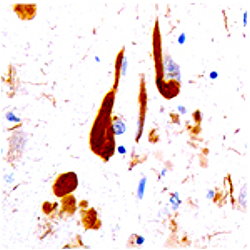

Tau-positive neurons (brown) in the hippocampus of a patient with Alzheimer's disease dilution of 1:1000) using Fluorescein (FITC)-labeled anti-Chicken IgY(1:500 dilution, Neuromics’ Catalog#:CH23101 ) as the secondary reagent.